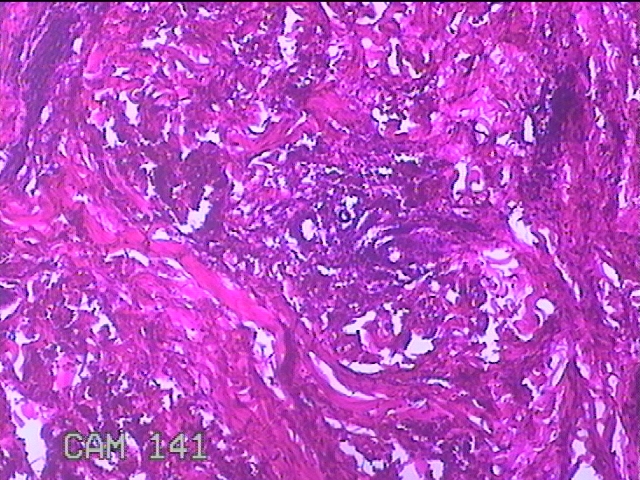

左臀部结节

性别

女

年龄

39岁

临床诊断

皮下结节

一般病史

发现左臀部多发性结节5年余。

标本名称

大体所见

灰白粉红色结节0.7x0.3x0.2cm一个,表面糜烂。